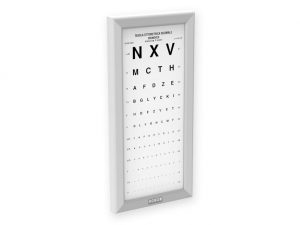

OTTOTIPO ULTRAPIATTO A LED – Decimali misti

455,00 € (555,10 € IVA incl.) -

Tavole optometriche, Tavole optometriche a LED ultrapiatte